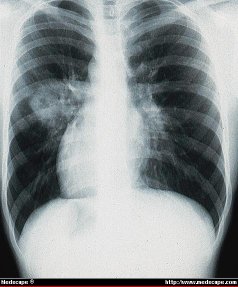

Enfermedad de Wegener con nódulos pulmonares. La radiografia de torax muestra los nódulos pulmonares que desarrolló una cavidad en un infiltrado izquierdo